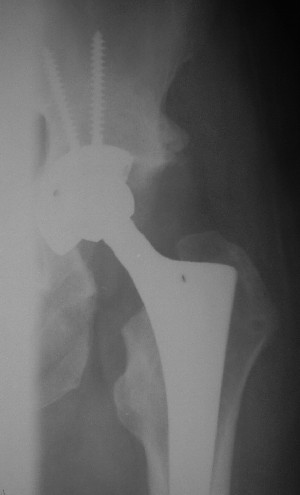

Уважаемые коллеги. Больной был оперирован в одну сессию 25 августа. Сначала на голень наложен спице-стержнвой аппарат. Затем выполнен остеосинтез вертлужной впадины Y-образным доступом. Пришлось дополнительно отсекать вертел. Шейка синтезирована спонгиозными винтами и спицами, вертел - спицами и стягивающей петлей. После операции находился на вытяжении 3 нед. Раны зажили первичным натяжением. Сейчас уже дома. Будет и дальше без нагрузки на левую ногу. Будем наблюдать в динамике. Ждем комментарии.